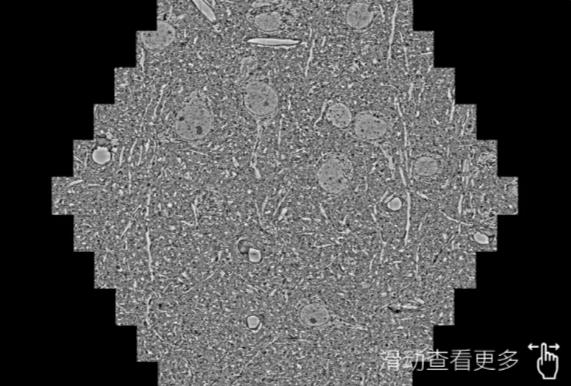

鼠脑切片。左图使用宜春蔡司宜春扫描电镜MultiSEM706对165μmx143pm面积区域成像,耗时仅需1.5秒。右图为鼠脑切片中30μm区域放大效果。样品由芝加哥大学B.Kasthuri提供。

使用蔡司高速宜春扫描电镜MultiSEM对1mm²人脑皮层组织进行高分辨成像,并对其中的各种细胞结构进行三维重构分析。左图展示了2x3mm²组织平面中锥体神经元的三维重构效果。右图显示了局部体积神经元三维重构。图像由哈佛大学chtman实验室提供,渲染图由D. Berger 制作。